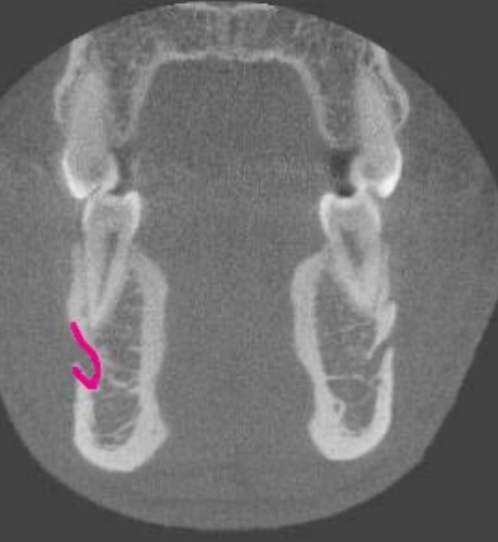

mental foramen

what is the structure indicated by the arrow